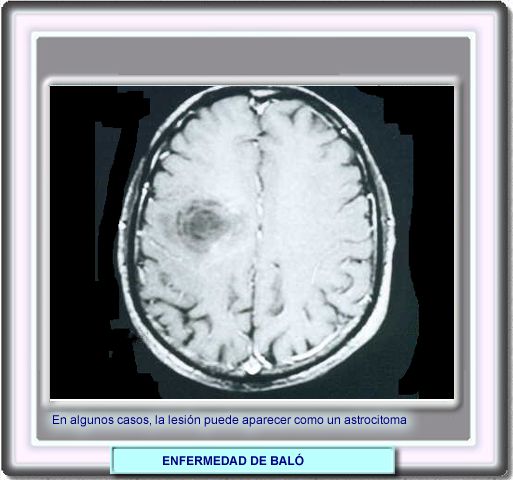

Se han descrito casos en los que las lesiones de la enfermedad de Baló son indistinguibles de un astrocitoma de grado bajo. En estos casos, el diagnóstico sobre puede establecerse anatomopatólicamente después de una biopsia estereotáctica